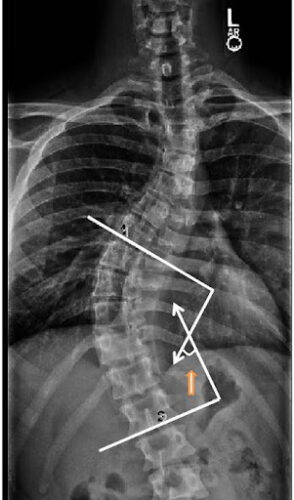

كيف يتم قياس زاوية كوب؟

تصوير الأشعة: يُجرى للمريض وهو واقف أو مستلقٍ.

تحديد الفقرات النهائية: اختيار الفقرة الأكثر ميلًا في أعلى وأسفل الانحناء.

رسم الخطوط: رسم خطين على الفقرات المائلة ثم قياس الزاوية الناتجة.

بدائل حديثة لقياس زاوية كوب

تقنية EOS: تصوير منخفض الإشعاع يعرض صورة ثلاثية الأبعاد للعمود الفقري أثناء الوقوف.

الرنين المغناطيسي أو الأشعة المقطعية ثلاثية الأبعاد: تكشف الدوران والانحناء الأمامي والخلفي.

طريقة زاوية دوران الفقرات : بديل واعد بدقة عالية تصل إلى ±3 درجات.